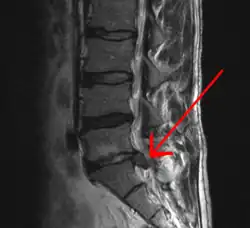

| Imagem de RNM de hérnia de disco lombar (seta) | |

Hérnia de disco/hérnia discal é a projeção da parte central do disco intervertebral (o núcleo pulposo) para além dos seus limites normais (a parte externa do disco, o ânulo fibroso). Ocorre geralmente póstero-lateralmente, em virtude da falta de ligamentos que sustentem o disco nessa região.[1]

O disco intervertebral é uma placa cartilaginosa que forma uma almofada entre os corpos vertebrais. Após traumatismos (quedas, acidentes automobilísticos, esforços ao levantar, entre outros), a cartilagem pode ser lesada, comprimindo raízes nervosas. Em qualquer local da coluna vertebral pode haver herniação discal.